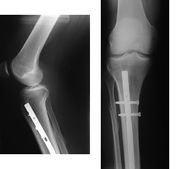

- Osteosynthesa znamená operační řešení, při kterém je kost zpevněna nejčastěji kovovým materiálem, kterým je nějaký druh nerezové oceli nebo titanu, který se po čase buď vyjme, nebo někdy i ponechá. Existuje řada metod, od jednoduchých cerkláží ocelovými dráty, přes šrouby doplněné dlahami až po nejrůznější systémy hřebování s předvrtáváním nebo bez něj (hřeb znamená navlečení nejčastěji dlouhé a duté kosti na pevný a dlouhý ocelový profil, který je na konci zafixován šrouby. Po čase se šrouby na jednom zpravidla distálním (vzdáleném) konci vyjmou, čemuž se říká dynamizace).